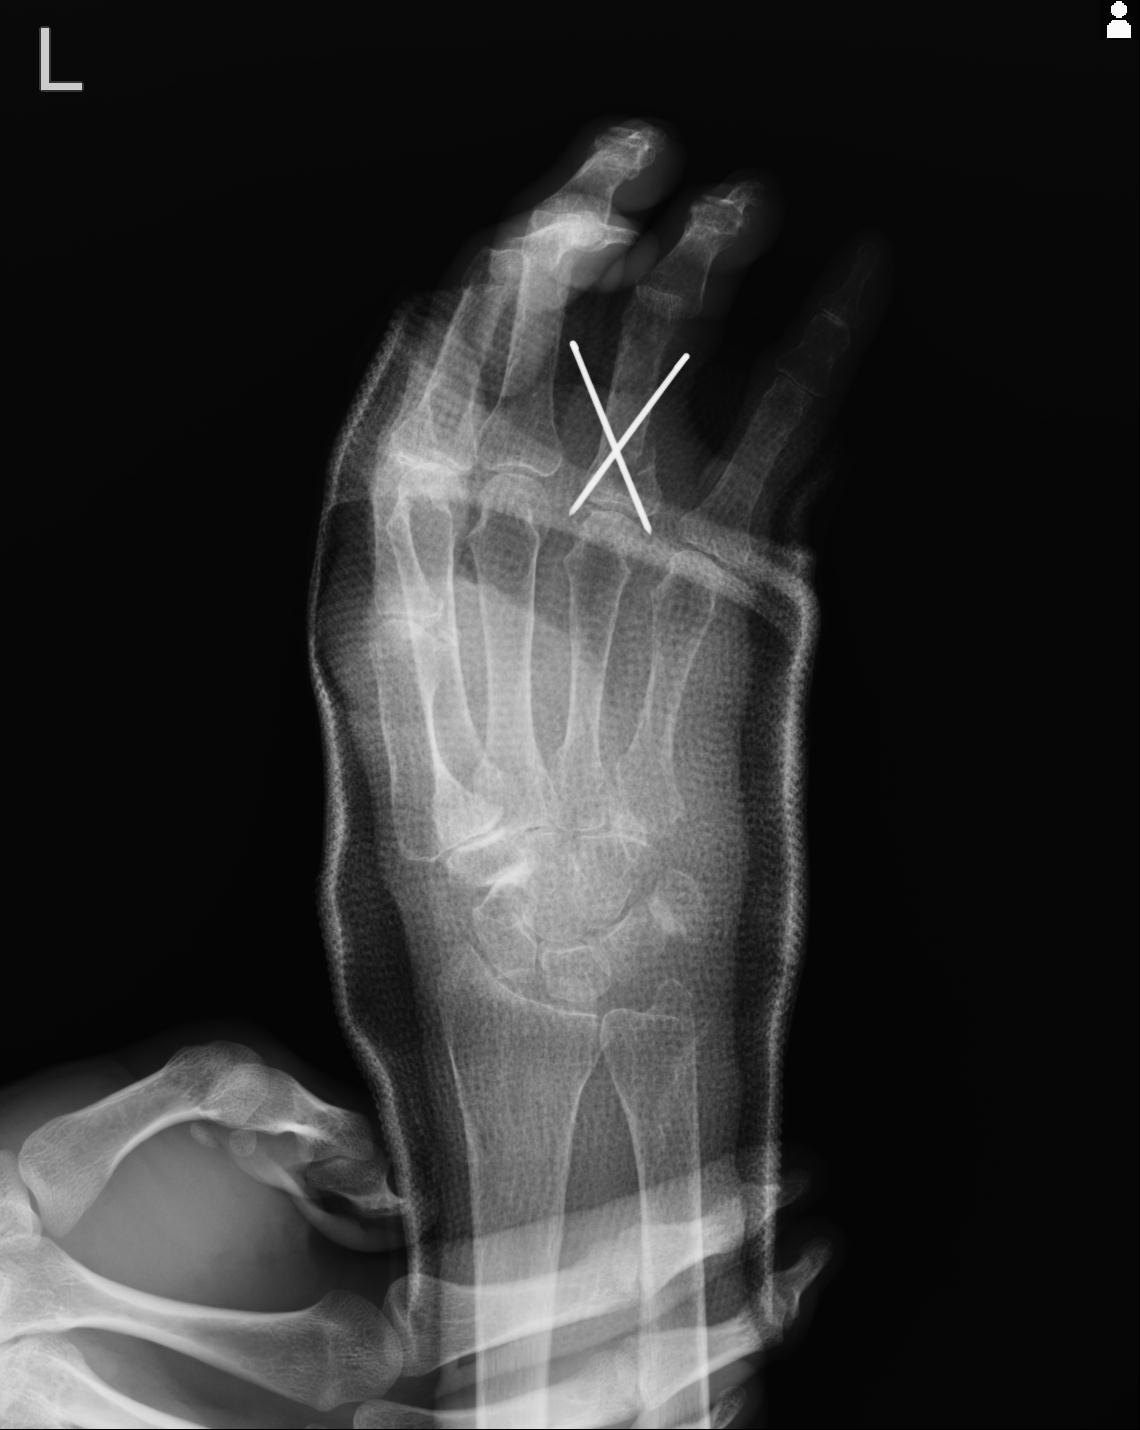

102860 1/21 (4R) 1/26 (4R) 3/15 左手 2R 91歳女性 左環指中節骨